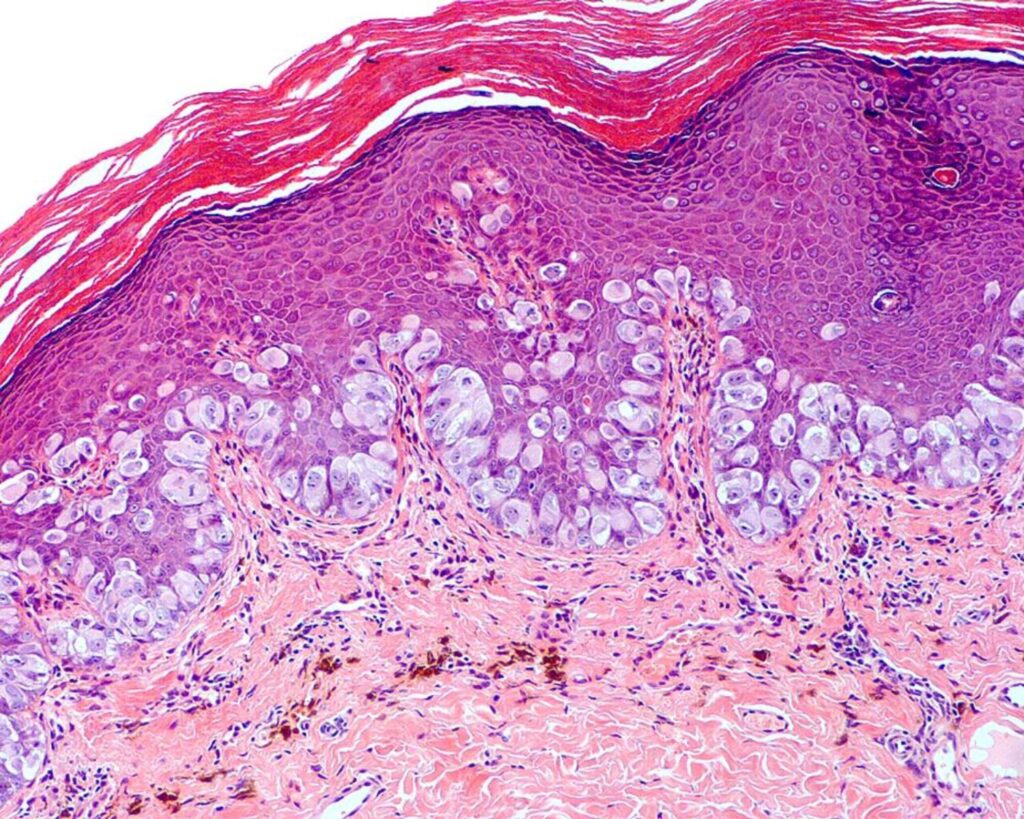

Generalidades de las infecciones fúngicas

Las infecciones fúngicas de la piel son causadas por la proliferación excesiva de hongos en la epidermis, la capa más externa de la piel. Estas infecciones pueden manifestarse de diversas…